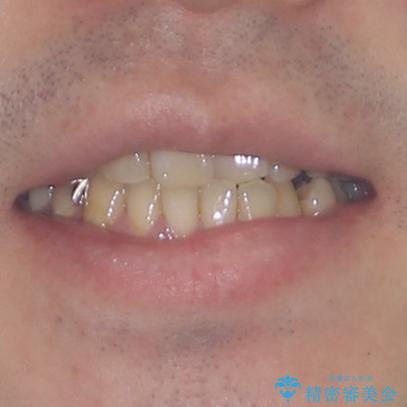

- デコボコした前歯をセラミックできれいに揃えたいとのことで来院された患者様です。

はじめは矯正治療の期間が長いことに悩んでいらっしゃいましたが、ある程度整えば満足するだろうとのことで、インビザラインにて矯正治療を行うこととしました。